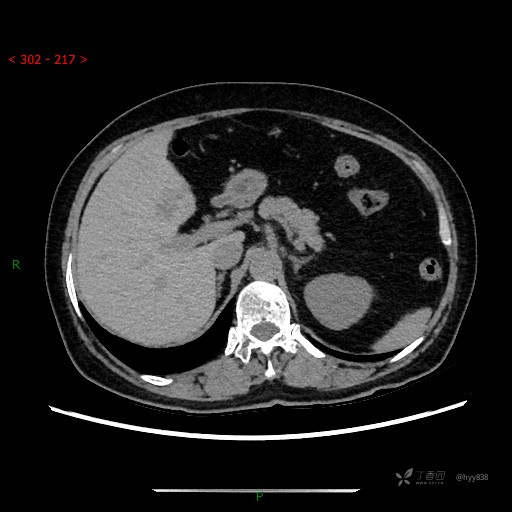

上腹部CT平扫